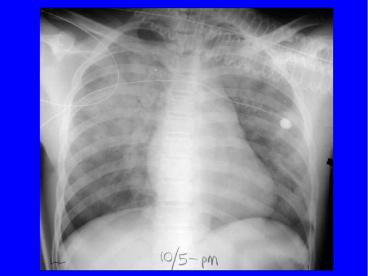

Méthodes dappréciation de lœdème pulmonaire

• Cliniques

• Imagerie (RxP, scanner, IRM, TEP)

Etiologies et modèles dœdème pulmonaire

• Clinique

• OAP hydrostatique ( OAP cardiogénique)

• OAP non-hydrostatique (ou lésionnel troubles

de perméabilité)

• SDRA par agression directe ou indirecte

• OAP mixte (neurogénique, altitude)